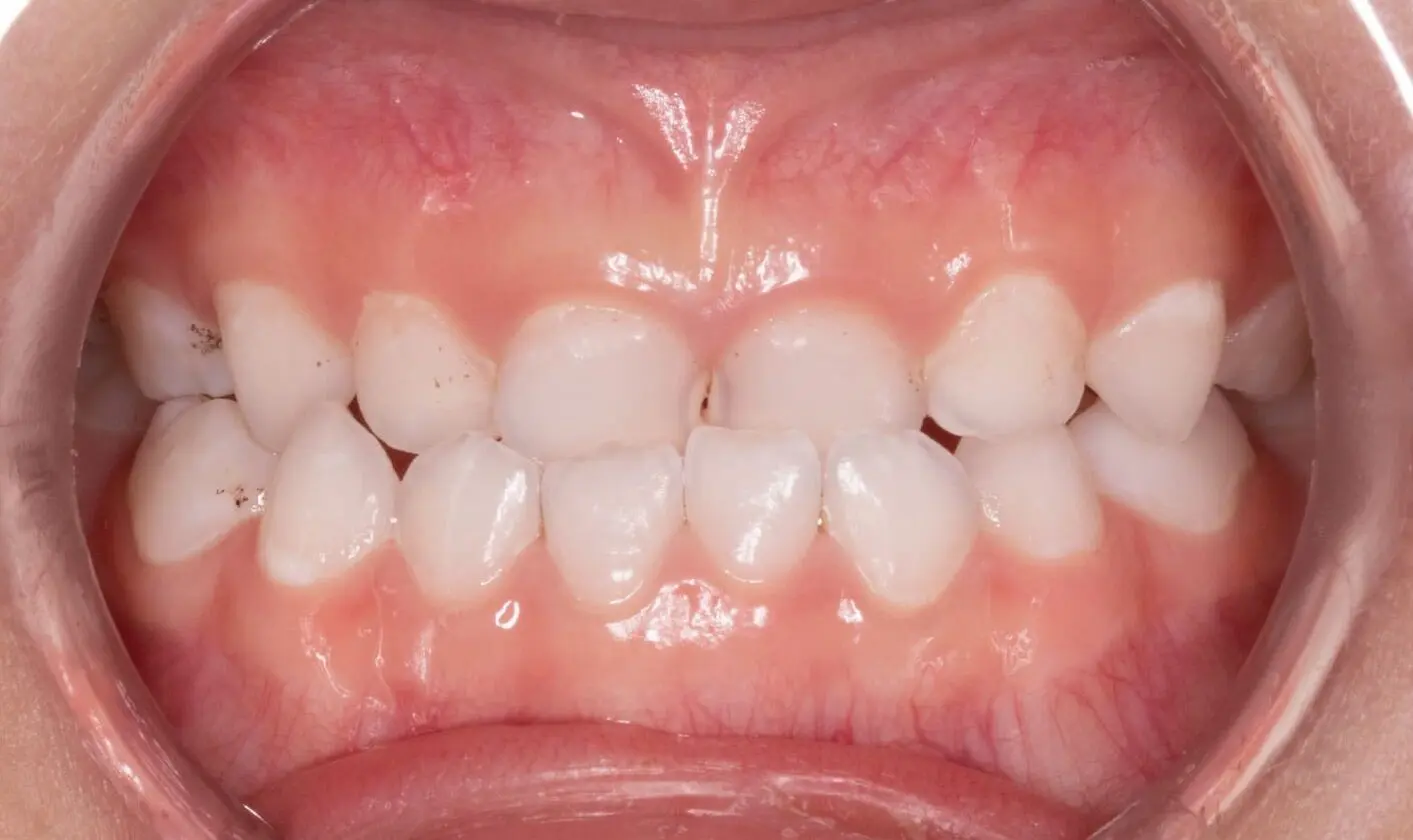

Expansion

Before